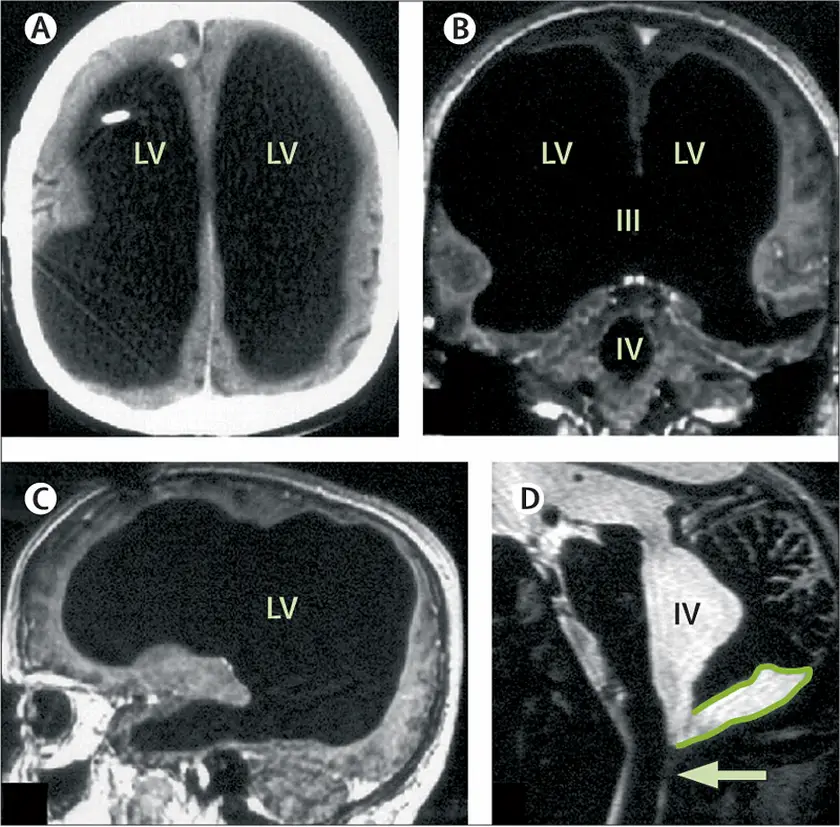

Bộ não có kích thước bất thường Bộ não của người đàn ông Pháp với bộ não có kích thước không bình thường

Các lần quét cho thấy có sự mở rộng lớn của tâm thất bên, thứ ba và thứ tư, lớp vỏ não rất mỏng và u nang fossa sau.

Không gian đen rộng lớn là chất lỏng tích tụ trong não của anh ấy. Feuillet et al. /The Lancet